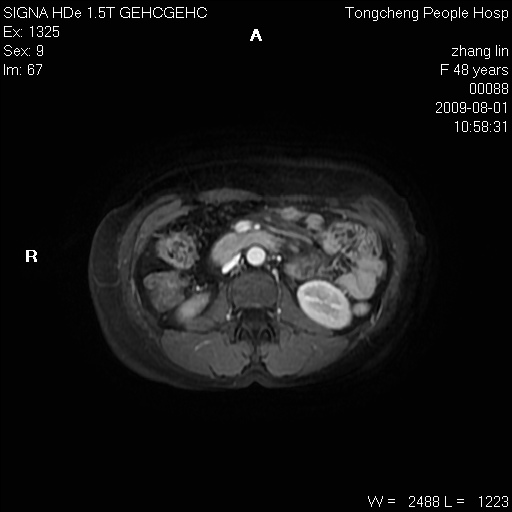

女,48岁。健康体检,彩超发现右肾占位性病变。平素健康。

临床诊断:右肾占位性病变,性质待定(囊肿?肿瘤?)。

上中腹部mr平扫+增强扫描,图像如下:

右肾上极见一类圆形病灶,t1wi呈等信号t2wi呈等高混杂信号,三期增强无强化,边界清---考虑囊肿出血。

同反相位均表现为等信号,病变无强化,考虑含蛋白的囊肿可能,弥散加权相或许有些帮助,